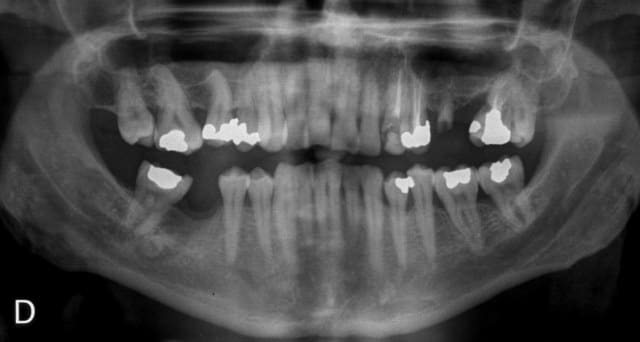

Pano initiale rhx4jg - Eugenol

Initial rir4cj - Eugenol

Radio1 nedqqo - Eugenol

Radio2 jxft6m - Eugenol

c'est quoi cette image radio au niveau de 46??

Je change un peu de sujet, mais sur la pano ; avez vous remarqué l'image peu banale au niveau de l'ancienne 38 ? On dirait presque un canal dentaire dédoublé.

Quelqu'un a un avis sur cette image ?

tu as la meme image a gauche qu'a droite, il s'agit peut etre simplement d'un manque de contraste radio...le canal dentaire est dessous...